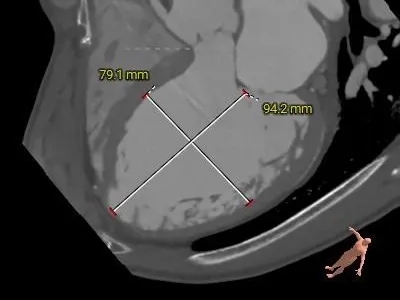

主动脉根部测量

ANNULUS

LVOT

SOV DIAMETER

周长75.7mm

周长径24.4mm

周长83.2mm

周长径26.5mm

内径

31.6*38.6*36.5mm

STJ

ASCENDING

AORTA

周长107.2mm

周长径34.1mm

周长116.2mm

周长径37mm